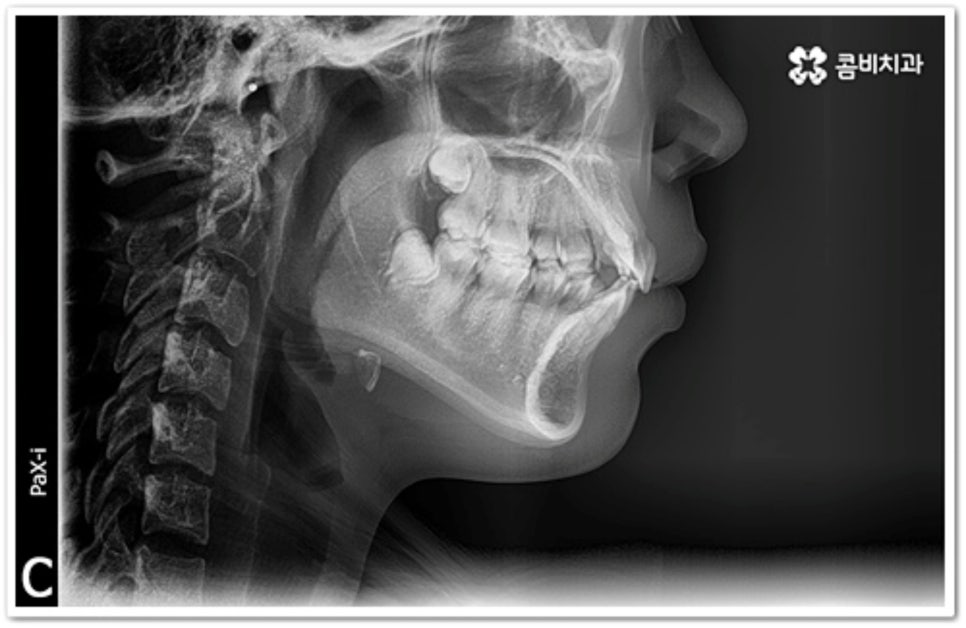

그러나 만약 덧니가 많고 부정 교합 정도가 심하거나 치아가 고르게 배열될 공간이 크게 부족하다면 덧니 발치 교정 치료를 진행하게 되는데, 이때 보통 치아 중에 기능이 가장 적은 소구치를 우선적으로 발치하게 되지만 (사진에서 확인할 수 있는 케이스) 환자분들의 상황에 따라 필요 없는 사랑니를 발치하고 어금니부터 뒤로 밀어 자리를 잡아주거나 충치 또는 짧아진 치근 등으로 심하게 손상된 치아가 있는 소구치를 우선적으로 발치하여 교정 치료를 진행하기도 하고, 필요시 임플란트와 병행하여 치료를 진행하는 경우도 있습니다. 따라서 먼저 자신의 상황에 대해서 면밀하게 검진을 받아보고 자세한 치료 계획에 대해서 의료진과 충분하게 상담해 보시는 게 좋을 거예요.

이와 같이 덧니라고 해서 치료가 다 똑같이 진행되는 것이 아니기 때문에 개개인의 치열, 교합 및 골격 형태와 턱의 구조적 특징을 명확하게 파악할 수 있는 정밀 검진 장비와 다양한 케이스 경험이 풍부한 숙련된 의료진, 체계적인 사후 관리 시스템이 있는 곳에서 진료를 받으실 것을 권유드리고 있어요.